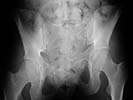

I did as suggested, I performed a 2-stage procedure (posterior sacral osteotomy and anterior take-down of left-sided rami fractures and anterior plate and percutaneous iliosacral screw fixation). It was a difficult and humbling experience. I felt as though the sacral osteotomy was complete and seemed so using intraoperative image views (inlet, outlet and true lateral of the sacrum) however after placing the distractor anteriorly I found that I could not see the sacrum well due to the bulk of the distractor itself. I then replaced it with radiolucent external fixation bars and noted widening of the left anterior SI joint.

Apparently my sacral osteotomy was not complete and the rotational correction (lateral and inferior) was occurring through the SI joint, at least anteriorly. An intraoperative x-ray showed definite improvement of the leg length discrepancy but not complete. I felt that in addition to the rotational correction the left hemipelvis also needed to move inferior as well. Due to the patient's small size, traction on her left leg simply produced pelvic obliquity and I really did not have a way of placing well leg traction which would require a post and at the same time obtain adequate intraoperative image views. Long and the short is I accepted a less than perfect reduction but with leg lengths now with less than 1 cm difference clinically and radiographically and I fused her left SI joint. No post-op nerve deficits. It was definitely a learning experience.

Any and all feed back is appreciated. Postop pics enclosed.

Probably the best treatment is avoiding this situation. Educate the individuals involved in her initial evaluation. Teach them the importance of clinical and radiographic patient evaluations. Teach them exactly how to examine an injured pelvis. If it had been examined initially, the clinical instability would have been obvious. The radiographs reveal bilateral, comminuted, displaced anterior ramus fractures along with a sacral fracture which violates the anterior, middle, and posterior portions of the sacrum (analogous to a complete sacroiliac dissociation)....a "3 column injury"(if you pretend that the sacrum is a vertebra), so to speak.

Intraoperative fluoro can be misleading regarding deformity corrections...maybe consider plain films when needed. Notice this lady's external rotation of the left hemipelvis postop and its impact on the acetabular coverage...see the inlet(caudal) view with attention to the ischial spine assymetry.